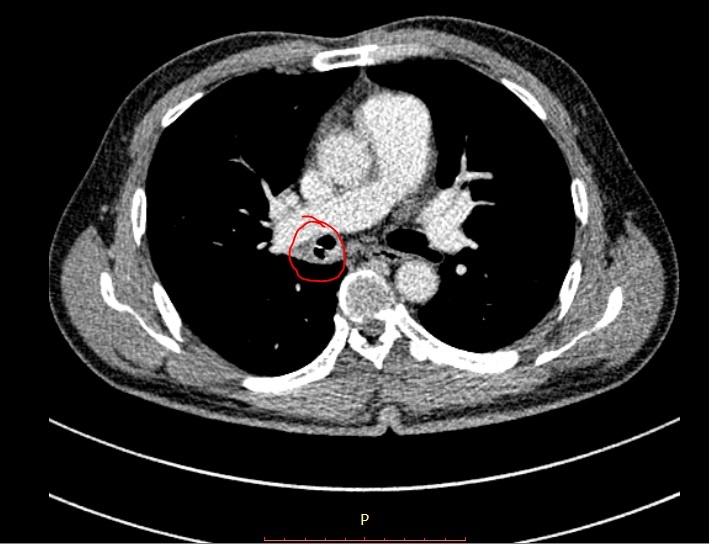

Các bác sĩ tại Bệnh viện quận Thủ Đức chỉ định bệnh nhân nhập khoa Nội tổng quát để theo dõi và điều trị. Bệnh nhân được yêu cầu chụp CT để tìm nguyên nhân. Kết quả ghi nhận vùng ở phế quản phải, nằm ở vị trí sát động mạch phổi có dị vật lạ không rõ bản chất, kèm viêm xung huyết quanh dị vật.

| Hình ảnh nội soi xương cá trong đường thở của người đàn ông. Ảnh: BVCC. |